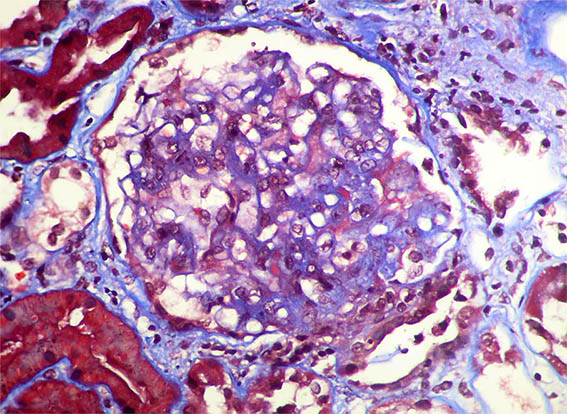

Figura 4. Tricrómico de Masson, X400. Lesión esclerosante segmentaria y posible pequeña semiluna epitelial en la parte inferior.

Figura 5. Tricrómico de Masson, X400.